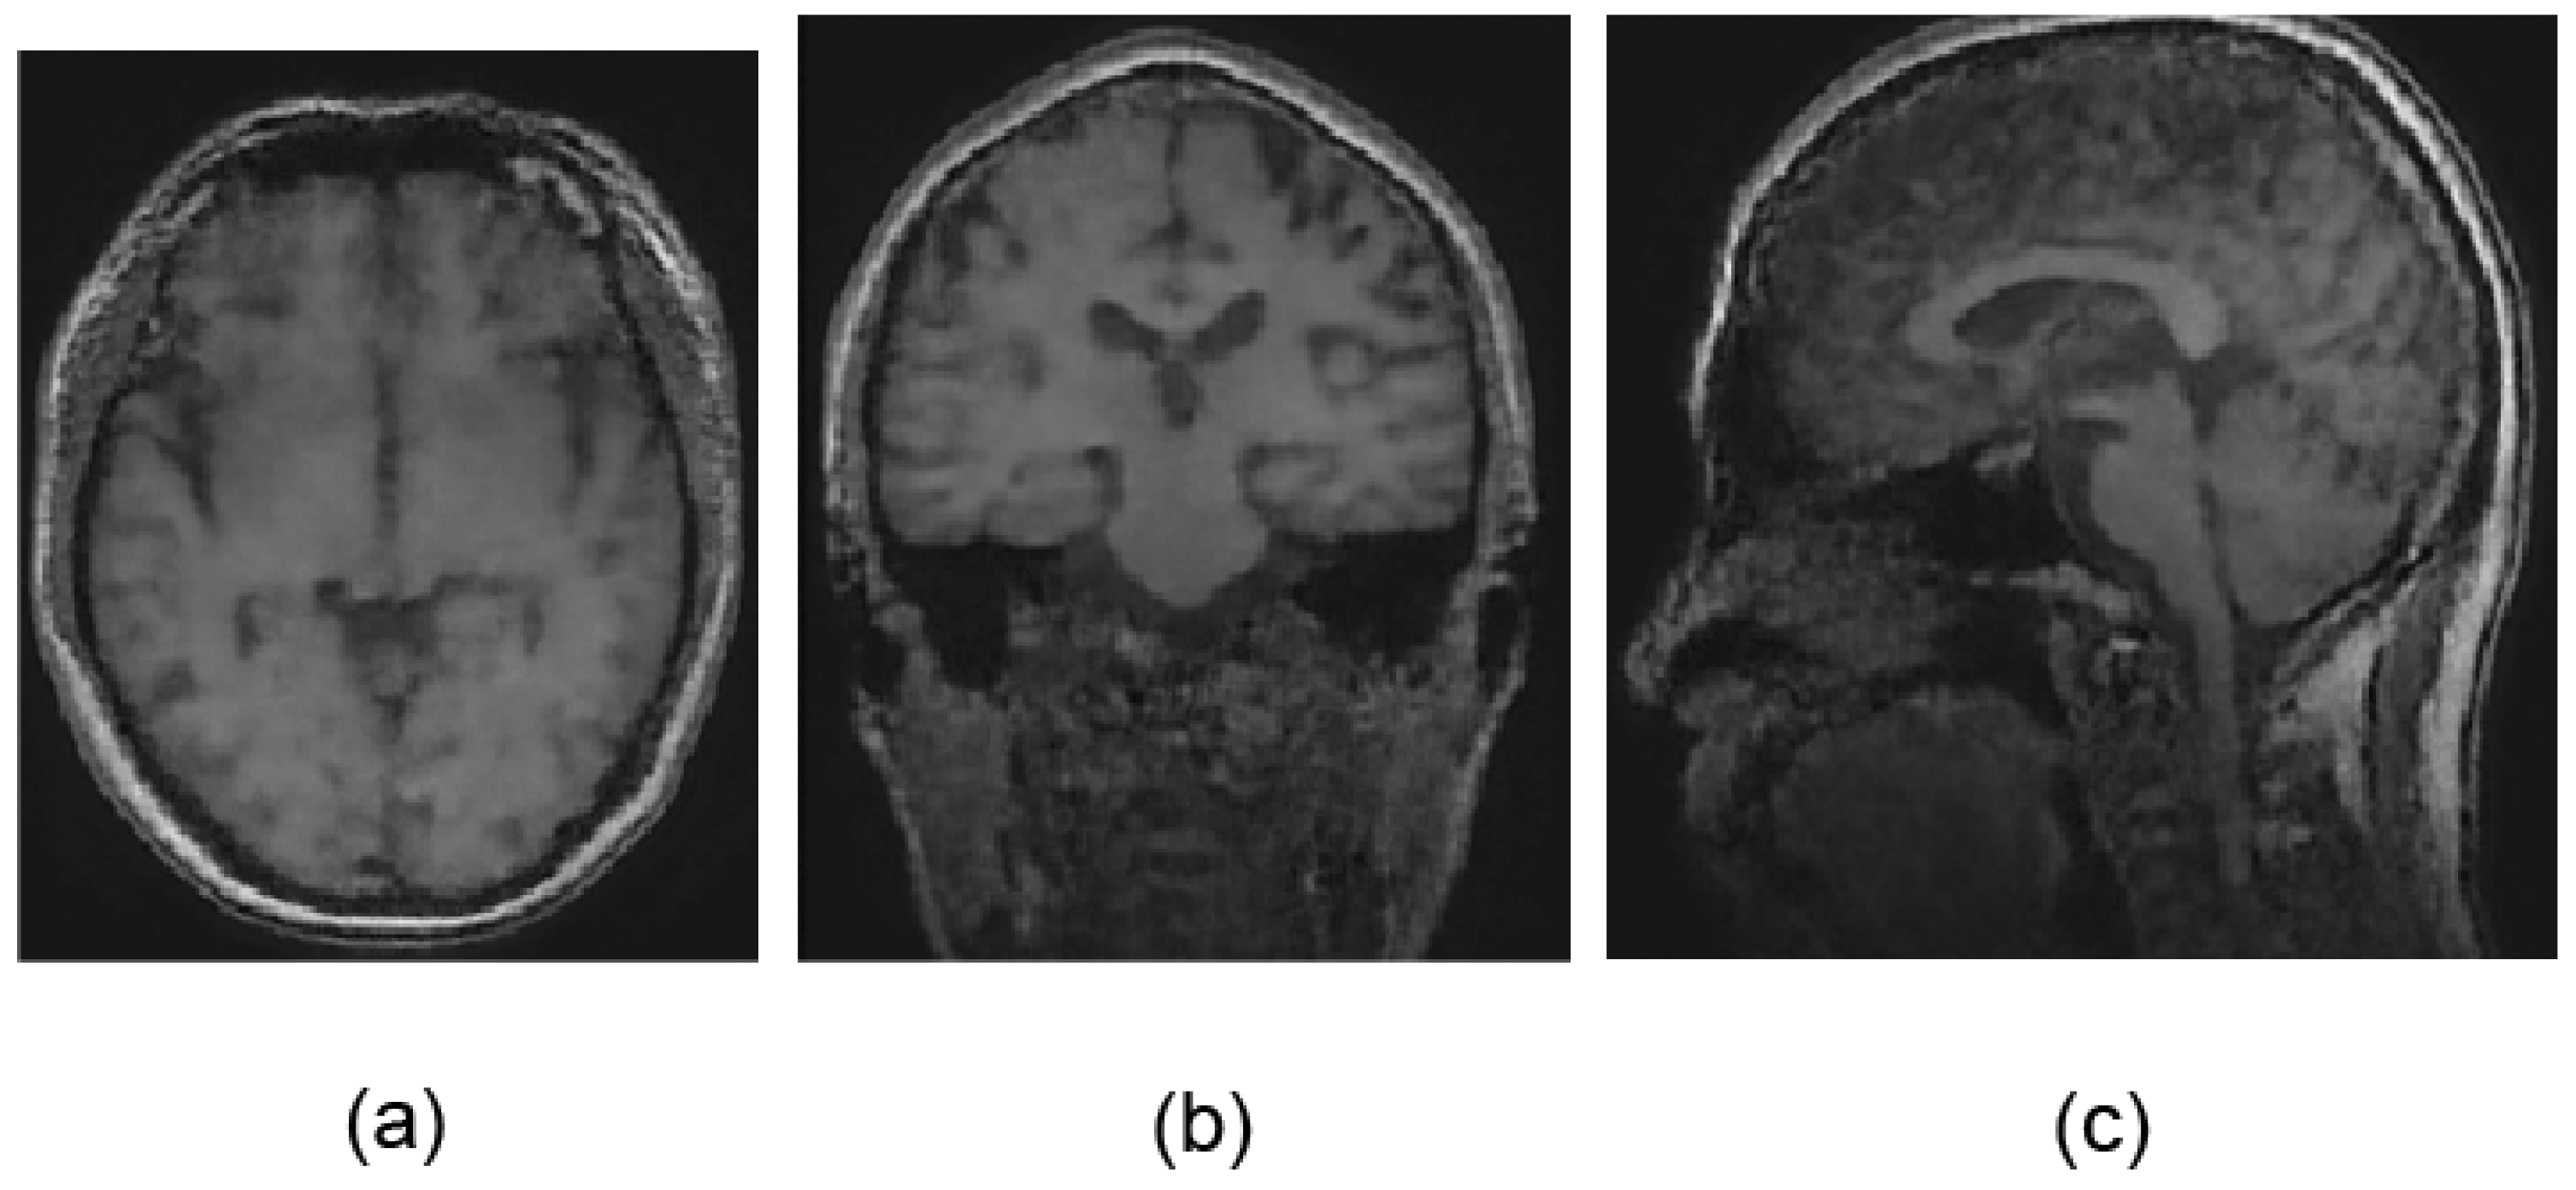

5.1. Unconditional Image Generation and Visual Evaluation